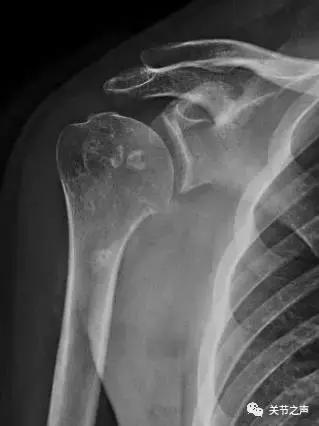

关节里长珍珠的症状:关节疼痛、卡压交锁例如:前不久,一位来自肇庆的许大姐因肩关节疼痛慕名来到暨南大学附属第一医院郑小飞主任门诊,X片显示他的肩关节长满了密密麻麻的“珍珠”。幸运的是,微创关节镜取“珍珠”是我们的看家本领,郑主任通过3个1cm的小切口就把他关节腔里的游离体全部取出,术后第二天开始康复功能锻炼。

除了肩关节,髋、膝、踝、肘、腕几乎全身各个关节都有可能长珍珠。